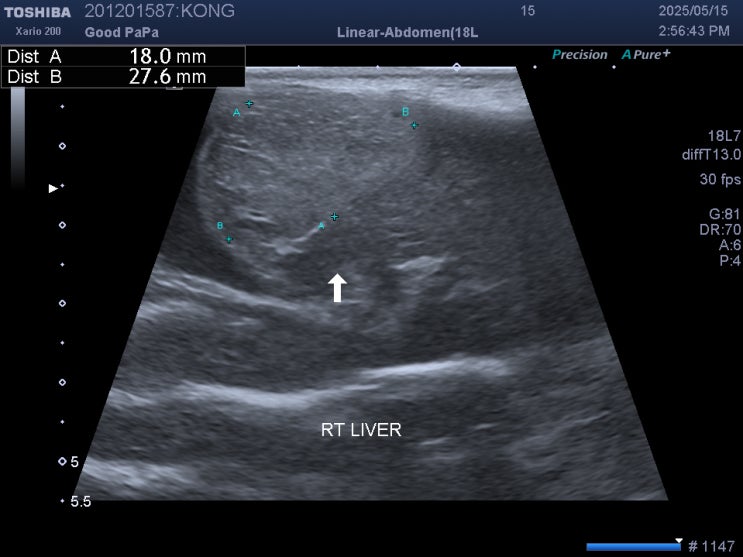

15살 말티즈 강아지 간종양 수술 없이 관리 후기 / 반려견 간종양 꼭 수술해야 하나요? / 댕댕이 간이 큰 이유, 원인 / 노령견 간암 증상, 치료, 관리법

안녕하세요~ 굿파파 수의사입니다. 벌써 점심시간이 지났네요 행복한 미소 가득한 하루 보내세요 오늘의 포...